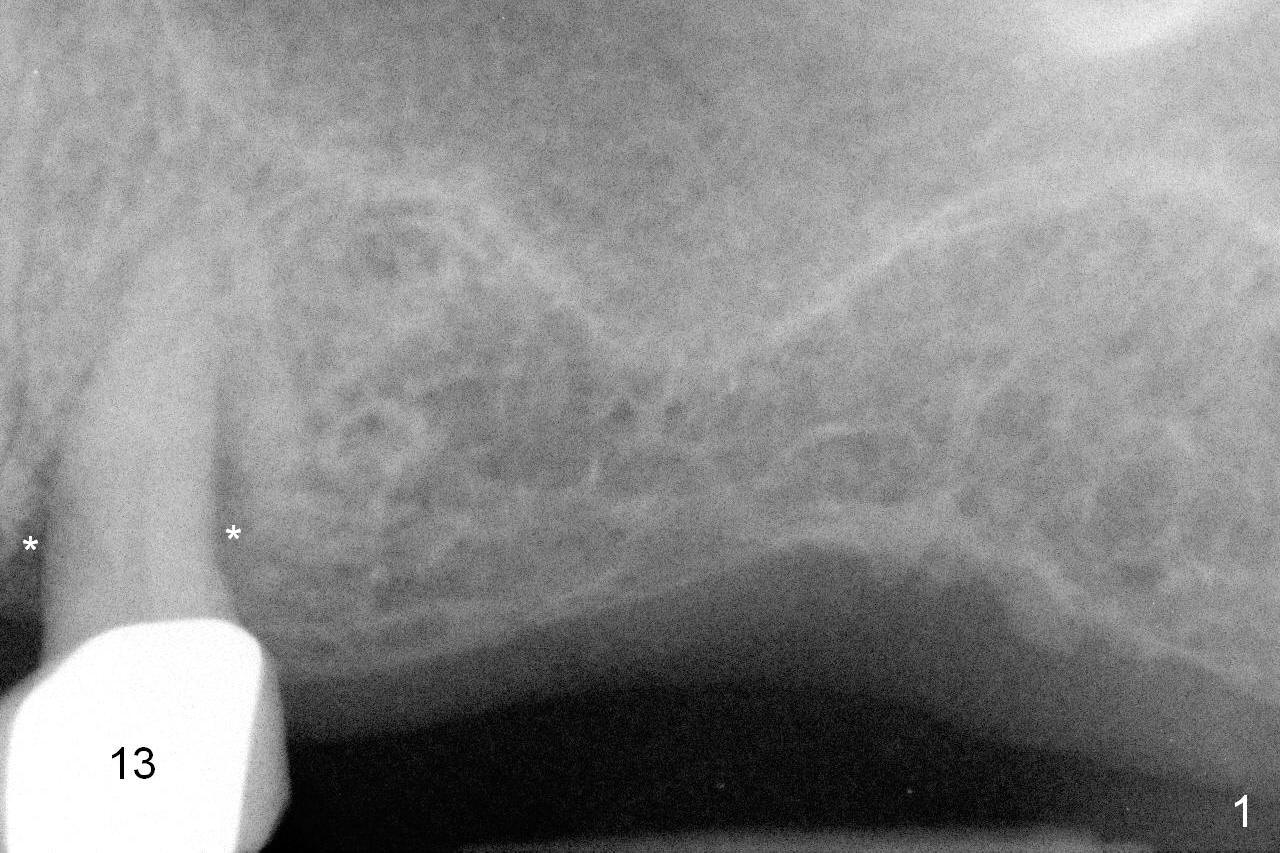

A 73-year-old woman is a possible bruxer with partial edentulism; the tooth #13 had increased periodontal ligament (pdl) space 4 years ago (Fig.1 *).  A 5x14 mm tissue-level implant is placed at the site of #14 (Fig.2).  The implant appears to be osteointegrated in 6 months (Fig.3).  There is crestal bone loss 8 months post cementation (Fig.4 *).  The persistent increased pdl at #13 is most likely associated with occlusal tramua from the tooth #19 (Fig.5 (13 months post cementation of #14)).  Three years post #14 cementation, the tooth #13 has mobililty II (Fig.6); bone density increases around the apical half of the implant (arrowheads).  Normally bone density is the highest coronally where functionality dictates.  This indicates the bone loss is getting worse at #14 as well.